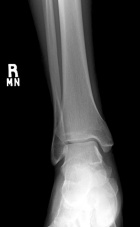

50 year old male with a several year history of right ankle mass, which the patient states has gotten larger in the past few months. On PE he has a tender, egg shaped mass in the distal posterior aspect of his left calf.

Zoom image: Radiological image Radiological image.